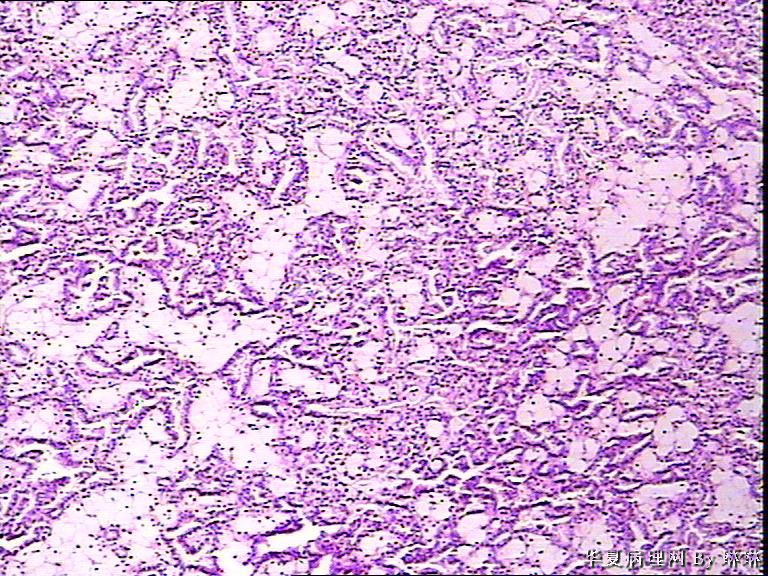

患者男性,50岁,右肾外伤可见一淡黄色圆形肿物,包膜完整,部分突出于肾表面,直径约3.5cm,切面淡黄色,质软。请各位看看,多多发表见解。

• 右肾肿瘤,请教!图1

图1

仔细看看有没有乳头状结构,要先考虑乳头状肾细胞癌,1 型。

考虑乳头状肾细胞癌

感觉还像透明细胞肾癌。

乳头状肾细胞癌